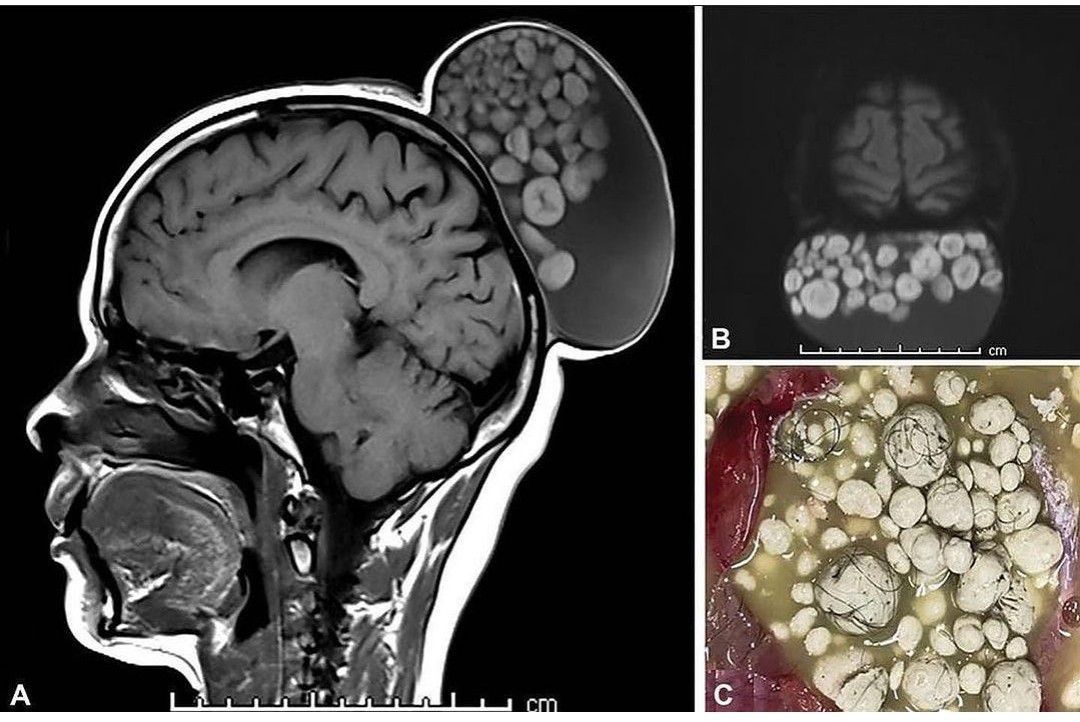

Teratoma: It is a type of tumor that can contain various types of tissues in the body such as hair, muscle and bone. Treatment usually involves surgery. In rare cases of malignant teratomas, chemotherapy or radiation therapy may be required. In this case, a 52-year-old woman presented with a painless swelling on her scalp that had gradually increased since childhood. An MRI showed multiple nodules of varying sizes floating in this large cyst, giving it a “bag of little balls” appearance (shown). After completing the surgical excision, the cyst was observed to contain sebum-like material, hard tooth-like structures, and several hairs. Histopathological examination confirmed the diagnosis of mature cystic teratoma, which are commonly found in gonadal tissues and in the head and neck region. On the head, they have a predilection for the orbit and scalp. .